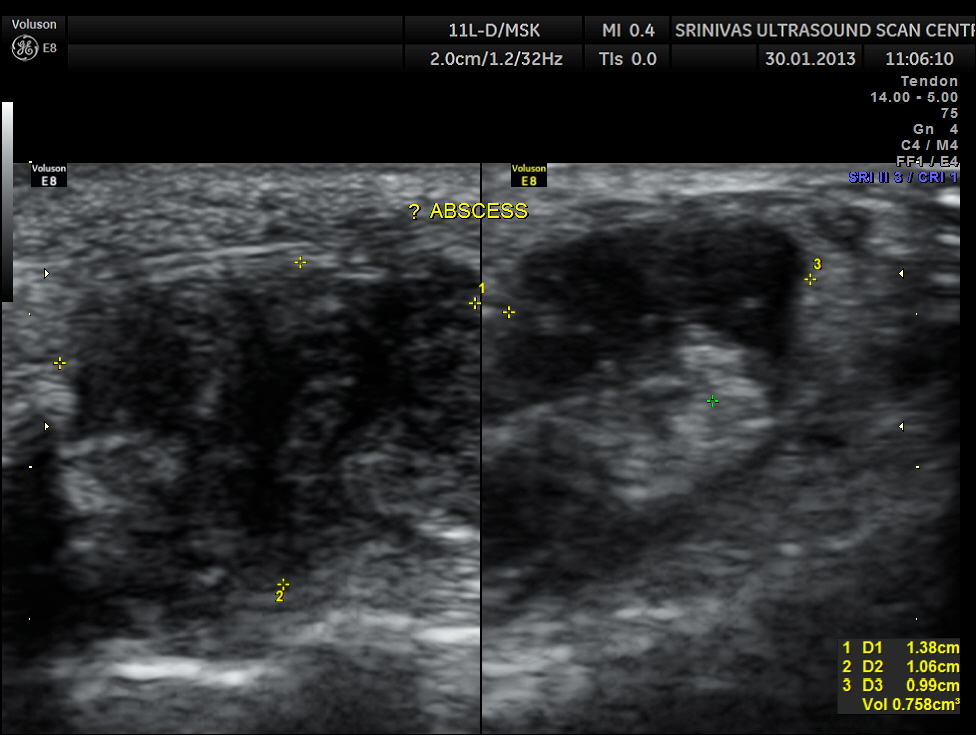

An indistinct hypo echoic mass was seen under a tendon and was well away from the surface of the bone .

Colour Doppler showed increased vascularity all around .

A diagnosis of an abscess in formation was offered and the child recovered well with appropriate treatment.